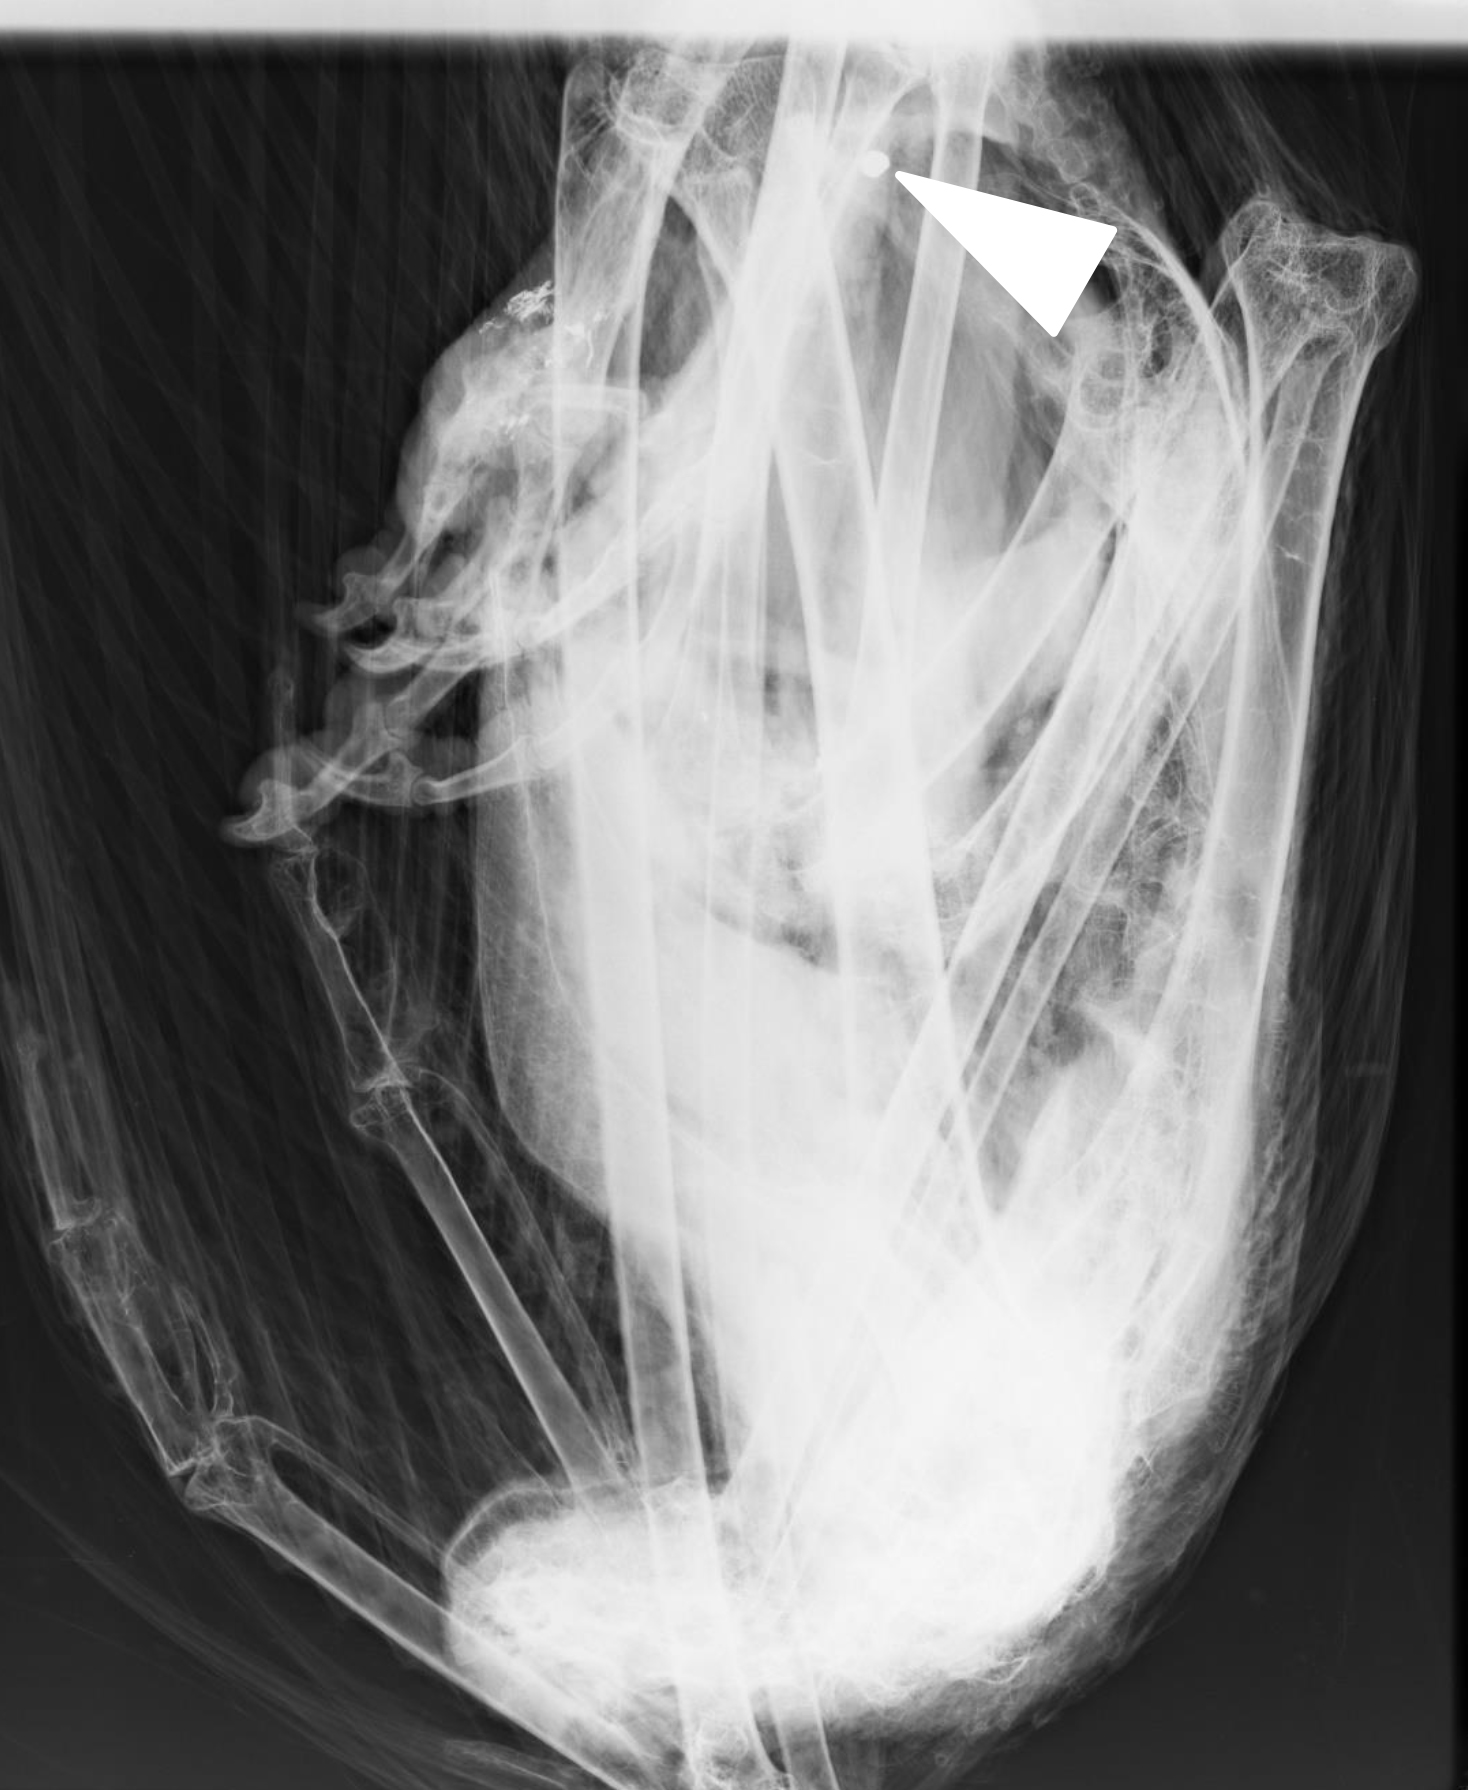

Röntgenbild des Gänsegeiers mit dem Befund von Bleigeschoss.

Bei der Untersuchung des Gänsegeiers am LGL stellte sich heraus, dass sich im Gewebe des Greifvogels ein stecknadelkopf-großes bleihaltiges Geschoss von rund fünf Millimetern Größe und nicht einmal einem Gramm Gewicht befand. „Damit ist erneut bewiesen, dass Blei selbst in geringsten Mengen in der Lage ist, auch einen bis zu zehn Kilo schweren und über einen Meter großen Geier zu töten“, erklärt Andreas von Lindeiner. Laut LGL-Befund wird bei Tieren schon ab 2–10mg/kg von einer Bleivergiftung gesprochen. „Die Analysewerte der Leber des Gänsegeiers ergaben eine Belastung mit 22 Milligramm Blei pro Kilo Gewebe“, erklärt der LBV-Biologe.